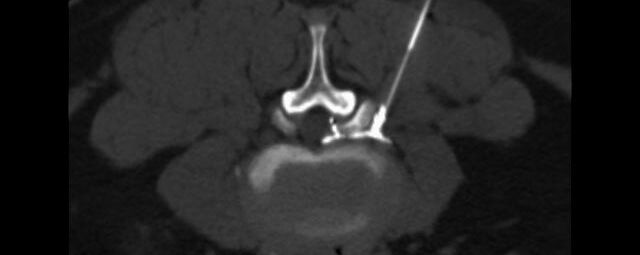

Wirbelsäule

• Darstellung von Frakturen, Tumoren und Bandscheibenveränderungen

Interventionelle Eingriffe

Durchführung am Standort im Diakonissenkrankenhaus

• z. B. Punktionen zur Gewebsentnahme

Schmerztherapie

(dazu mehr auf der Seite Schmerztherapie)

Der Multislice-Scanner ermöglicht eine dem aktuellen Stand der Technik entsprechende, leitliniengerechte diagnostische Untersuchung sämtlicher Körperregionen. Darüber hinaus gestattet der neue Computertomograph auch eine für Arzt und Patient bequeme Durchführung CT-gestützter Interventionen wie z.B. Schmerztherapien der Wirbelsäule.